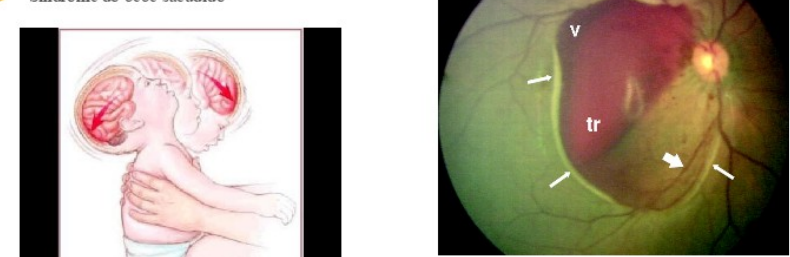

<p>EMERGÊNCIAS OFTALMOLÓGICAS</p><p>· TRAUMA</p><p>· OLHO VERMELHO</p><p>· BAIXA VISUAL</p><p>Segmento posterior (corpo ciliar para trás) é mais grave. Perfuração com laceração de esclera é muito mais grave.</p><p>SINAIS DE TRAUMA, FRATURAS DA ÓRBITA:</p><p>-EPISTAXE</p><p>-EXO OU ENOFTALMIA</p><p>-DIPLOPIA</p><p>-PERDA DA VISÃO</p><p>-BLEFAROHEMATOMA: hematoma das pálpebras</p><p>-ENFISEMA PALPEBRAL: presença de ar embaixo da pálpebra, advindo dos seios faciais. Pedir RX para identificar fratura.</p><p>-DISTÚRBIOS DA MOTILIDADE: aprisionamento do músculo na fratura, contido em processo inflamatório localizado havendo restrição do movimento.</p><p>-CELULITE OU ABSCESSO PERIORBITÁRIO: relacionado a sinusite pré-existente.</p><p>TRAUMAS MECÂNICOS:</p><p>- SUPERFICIAL</p><p>- CONTUSO</p><p>- PENETRANTE - com ou sem corpo estranho</p><p>- PERFURANTE</p><p>TRAUMAS NÃO MECÂNICOS – QUEIMADURAS:</p><p>-Térmicas</p><p>-Químicas</p><p>Córnea inervada por nervo facial e ramo oftálmico do nervo trigêmeo. Extremamente inervada, dói mais que lesão na retina e nervo óptico.</p><p>TRAUMATISMO CRANIANO POR MAUS TRATOS:</p><p>Síndrome do bebê sacudido. Hemorragia subhialoide. O vítreo é envolto por uma membrana fina hialoide, grudada na retina. Quando ocorre separação do vítreo e da retina, ocorre hemorragia subhialoide. Esse sangue deve ser drenado para evitar coagulação, fibrose, alteração macular irreversível.</p><p>A visão se desenvolve até os 7 anos de idade.</p><p>SINAIS DE TRAUMA OCULAR:</p><p>Hiposfagma: Hemorragia subconjuntival, entre conjuntiva e esclera. Não é grave. Normalmente associado a picos de HAS não tratata, manobra de valsalva. Hiposfagma de repetição deve pensar em coagulopatias.</p><p>Hifema: sangue na câmara anterior. O trauma vai mobilizar os tecidos cansando ruptura de vasos da íris, ou do ângulo da câmara anterior. Pode ter hemorragia contida na parte anterior do olho. O humor aquoso é produzido no corpo ciliar e drenado no seio da câmara anterior, pelo canal de Schlemin. Se houver hemorragia na parte anterior, o canal de drenagem do humor aquoso vai ser obstruído, havendo aumento da pressão intraocular (glaucoma causado por hemorragia). Deve usar anti inflamatórios, drogas para baixar a pressão intraocular. Se não resolver, deve ir para cirurgia.</p><p>Hipópio: pús na câmara anterior. Tratamento o quanto antes. Bactéria no olho se dissemina muito rápido.</p><p>Atalamia: perda do espaço entre a íris e a córnea. Deslocamento do cristalino para frente, empurrando a base da íris, indo de encontro a córnea, fechando o ângulo da câmera anterior, aumento da pressão intraocular, glaucoma. Muita dor. Deve baixar a pressão do olho o quanto antes, com manitol e cetazolamida VO.</p><p>Corectopia</p><p>Catarata: Qualquer trauma perfurante, se tocar no cristalino é considerado catarata. Rompe a integridade da lente, o humor aquoso vai entrar. Deve remover o quanto antes e fechar o olho. Acima de 6 horas a íris é removida e ressecada.</p><p>Avaliação inicial: extensão do trauma.</p><p>De acordo com a história deve ter em mente um diagnóstico. Se o olho traumatizado for o direito, fecha o esquerdo, projeta uma luz, e pede para ele se está percebendo.</p><p>Percepção e projeção luminosa: foco luminoso, identifica se está vendo a luz em várias incidências. Se não enxerga se caracteriza como amaurose. Deve evitar pressão sobre o globo ocular.</p><p>· Acuidade visual.</p><p>· Evitar pressão sobre o globo ou a manipulação do mesmo (exceção: queimaduras químicas).</p><p>· Analgesia parenteral</p><p>· Não tentar remover tecidos necróticos ou coágulos</p><p>· Vacina anti-tetânica</p><p>- mais de 6 horas</p><p>- laceração muito contaminada</p><p>- perfuração profunda</p><p>-> trauma contuso envolvendo vítreo e retina, o deslocamento de retina faz com que o paciente refira moscas voantes, fenômenos luminosos (flashes, luzes, raios: fotopsias, flotters).</p><p>CORPO ESTRANHO:</p><p>Conjuntiva, córnea (dor, olho vermelho, fotofobia, lacrimejamento, embaçamento visual, todas as queixas relacionadas com a superfície ocular), intraocular</p><p>Conduta CE intraocular:</p><p>Anestésico, cotonete umedecido. Se não sair, encaminhar, não ficar tentando tirar.</p><p>· RX órbita</p><p>· CT crânio</p><p>· US ocular</p><p>· TRATAMENTO CIRÚRGICO (OFTALMOLOGISTA)</p><p>LACERAÇÃO VIA LACRIMAL?</p><p>Não remover corpo estranho. Tratamento cirúrgico. Encaminhamento!</p><p>Epífora: doenças da córnea ou de via lacrimal.</p><p>DACRIOCISTITE – CELULITE:</p><p>Doença de via lacrimal.</p><p>Crianças prematuras podem nascer com o canal da lágrima até o meato inferior obstruído.</p><p>Canalículo superior e inferior drenam para um ducto dentro do nariz, onde há a válvula de Hasner, que quando nascemos, já está aberta. Nos prematuros, podem nascer com a válvula fechada/parcialmente fechada. Há epífora unilateral (epífora bilateral ocorre em glaucoma congênito).</p><p>Deve fazer massagem, pois pretende que essa válvula abra, com compressa morna concomitante. Isso antes de haver dacriocistite.</p><p>Até os 9 meses só faz massagem e aguarda para ver se a válvula abre. Se não abrir deve fazer sondagem, com sedação, passa a sonda, e mecanicamente rompe essa membrana.</p><p>Se não resolver, e desenvolver a dacriocistite, deve fazer encaminhamento imediato ao pediatra com terapia sistêmica EV, muito grave, e após a resolução do quadro, fazer a sondagem.</p><p>A celulite é quando o processo infeccioso acomete todo o globo ocular, causada por trauma ou por dacriocistite que complicou. Encaminhar!</p><p>TRAUMA OCULAR TÉRMICO:</p><p>Frequente, mais em homens; quando uma substância altera bruscamente a temperatura do olho (solda);</p><p>Geralmente as queimaduras térmicas são restritas ao local acometido (ceratite actínica).</p><p>As lesões são mais graves quando há perfuração ou presença de corpo estranho retido.</p><p>O médico generalista:</p><p>-Lavagem dos olhos e oclusão ocular (pomada ATB e tampão bem fixo para evitar de piscar e movimentar a pálpebra sobre a córnea).</p><p>-Controle da dor: analgesia sistêmica (tilex)</p><p>-Encaminhar.</p><p>TRAUMA OCULAR QUÍMICO:</p><p>Acidentes domésticos/ local de trabalho. Podem ser causadas por ácidos ou bases.</p><p>Ácidas: necrose importante e a coagulação das proteínas.</p><p>Ácido sulfúrico (ex: uso industrial como catalisador), ácido sulfuroso (ex: componente da chuva</p><p>ácida) e ácido acético (ex.: vinagre).</p><p>Básicas: álcalis, mais graves (combinação sucessivamente com as proteínas tissulares)</p><p>Amônia (ex: produtos de limpeza, detergentes, amaciantes de roupas, fertilizantes);</p><p>Hidróxido de sódio ou soda cáustica (ex.: fabricação de sabão caseiro);</p><p>Cal ou óxido de cálcio (ex: uso industrial como regulador de pH, componente de argamassa).</p><p>Lavar muito, cerca de 30 minutos o olho. Controle da dor sistêmica, oclusão.</p><p>CONDUTA NO TRAUMA OCULAR QUÍMICO:</p><p>· Irrigação copiosa com solução isotônica ou água limpa</p><p>· Dupla eversão das pálpebras: para ver se tem algum componente abaixo</p><p>· Desbridamento (oftalmologista)</p><p>· Admissão hospitalar</p><p>· Graduação da gravidade: transparência da córnea e isquemia do limbo. Quanto mais difícil de ver a íris, pior o prognóstico.</p><p>· Pomada ATB</p><p>· Esteróides tópicos: retarda a inflamação</p><p>· Cicloplegia: diminui a inflamação do tecido uveal.</p><p>· ATB tópico: como o maxinom, passar dentro do olho, fechar e fazer tampão firme.</p><p>OLHO VERMELHO (inflamação, dilatação venosa):</p><p>CONJUNTIVITES: inflamação da conjuntiva</p><p>CERATITES: inflamação da córnea</p><p>BLEFARITES/MEIBOMITES</p><p>HORDÉOLO</p><p>HEMORRAGIA SUB CONJUNTIVAL: hiposfágma</p><p>PTERÍGIO/PINGUÉCULA</p><p>EPISCLERITE/ESCLERITE: esclerite é todo o globo ocular. Episclerite da esclera superficial, somente uma parte do globo ocular. Diagnóstico diferencial: colírio com fenilefrina (vasoconstrictor), episclerite some.</p><p>GLAUCOMA: traumático, por catarata, etc. Dor ocular, cefaleia, aumento da pressão do olho, olho vermelho difuso, visão embaçada, halus (olha para a luz), vômito, náusea. Deve desidratar o vítreo e encaminhar para um especialista.</p><p>UVEÍTES</p><p>PERDA DA VISÃO COM DOR AGUDA</p><p>GLAUCOMA AGUDO:</p><p>Dor, halos luminosos. Náusea, vômito. Turvação visual. Hiperemia. Pupila fixa em média midríase</p><p>Diagnóstico diferencial: enxaqueca, AVE hemorrágico.</p><p>TRATAMENTO:</p><p>· ANALGESIA</p><p>· Redução da PIO com colírios:</p><p>· Inibidores da anidrase carbônica/β - bloqueador tópico/α2- agonista tópico</p><p>· Hiperosmóticos (glicerina/manitol)</p><p>· Quebra do bloqueio pupilar (YAG laser – iridotomia)</p><p>PERDA DA</p><p>VISÃO AGUDA – sem dor:</p><p>- hemorragia vítrea e macular/ oclusão venosa ou arterial: história de aterosclerose, etc.</p><p>PERDA DA VISÃO AGUDA – com dor:</p><p>- arterite temporal/ neurite óptica: localiza a dor em um ponto, no olho. Normalmente idosos, homens. Aviso do que pode estar por vir, pois pode causar neuropatia isquêmica, perdendo a visão. Encaminhar paciente para neurologista para avaliação, diagnóstico por biopsia.</p><p>PERDA DA VISÃO TRANSITÓRIA:</p><p>- enxaqueca/ insuficiência carotídea</p><p>OUTRAS CAUSAS DE BAIXA VISUAL:</p><p>- neurorretinites/ retinopatia diabética/catarata/glaucoma crônico, DR, DMRI</p><p>image6.png</p><p>image7.png</p><p>image8.png</p><p>image9.png</p><p>image10.png</p><p>image11.png</p><p>image1.png</p><p>image2.png</p><p>image3.png</p><p>image4.png</p><p>image5.png</p>